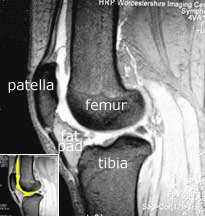

Note the relationship of the fat pad to the patellar tendon, and hence the extensor mechanism. It fills the space from the patellar tendon all of the way to the cruciate ligaments. In fact, it also extends sideways, making the bulge that one can often see in a normal knee on either side of the patella (red arrow). Normally the fat pad is not attached to either the meniscus or the patella, and is separated from the patellar tendon by the deep infrapatellar bursa.

With arthrofibrosis fat pad the fat pad becomes thickened and fibrosed, and the deep infrapatellar bursa can be obliterated. The fat pad can become adherent to the anterior horn of the meniscus and to the patella, and via the obliteration of the deep infrapatellar bursa it becomes adherent to the patellar tendon also. This thickened fat pad may also become tethered to the intercondylar notch where the cruciate lies.

Note also from the MRI that the fat pad is truly in contact with the bony lower edge of the patella. If that fat pad is scarred and contracted, can you imagine how it can pull the patella downward?

The cruciate ligaments, by their complex position of the knee, anchor the femur to the tibia. Superimpose in your mind’s eye the photograph above upon this illustration of the intercondylar notch and the cruciate ligaments. Imagine how the fat pad tucks into the femoral notch, and how easily it and the cruciates can both be involved in the arthrofibrotic scarring process.

The two menisci can also be seen in the illustration, which are located between the tibia and femur. They are held in position around their outer edges by the coronary ligaments, which attach them to the tibia.